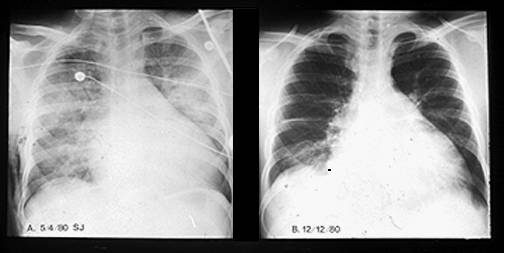

CARDIOMIOPATIA PERIPARTUM

Este o forma de CMD de cauza necunoscuta ce survine in ultimul trimestru al sarcinii sau in primele 6 luni dupa nastere.

Tabloul clinic include fatigabilitate, dispnee progresiva, palpitatii, dureri toracice, tuse, hemoptizii (prin tromboembolism pulmonar). Rapid se dezvolta o insuficienta cardiaca biventriculara. Pot surveni embolii sistemice si pulmonare.

Evolutia este variabila - la jumatate din bolnave modificarile morfologice, dilatatia cardiaca si fenomenele de insuficienta cardiaca dispar in 6-12 luni. La jumatate evolutia este continua si rapida spre exitus sau lenta spre insuficienta cardiaca cronica.